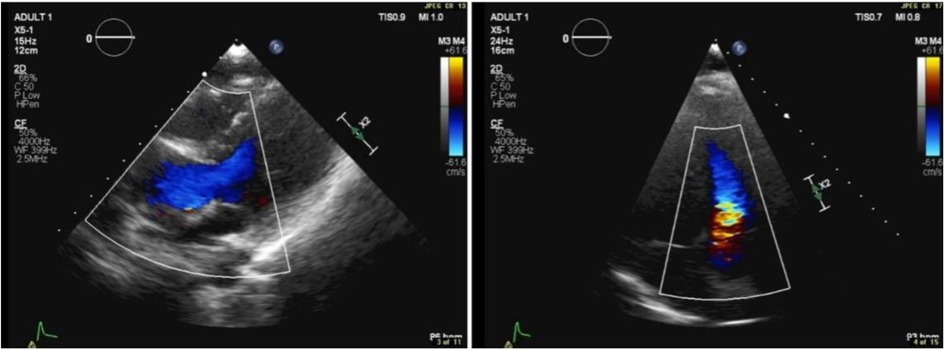

Figure 1. Transthoracic echocardiographic color Doppler showing flow turbulence through the RV-PA conduit. Peak gradient: 25 mmHg; mean gradient: 13 mmHg.

In April 2018, transthoracic echocardiography was performed as part of the patient's follow-up. The imaging revealed a dilated aortic root, with the sinus of Valsalva measuring 3.1 cm. Some cardiac valve anomalies were present, including mild-to-moderate tricuspid regurgitation (TR), and trace mitral regurgitation (MR). There was no evidence of shunting at the atrial, ventricular, or arterial levels. The other cardiac chambers are grossly normal in size, thickness, and systolic function and hemodynamic assessment showed increased flow velocity at the level of the conduit to the pulmonary artery branches, with a peak systolic gradient of 25 mmHg and a mean gradient of 13 mmHg. Right ventricular (RV) function remained within normal limits, and there were no signs of pericardial effusion or aortic coarctation.